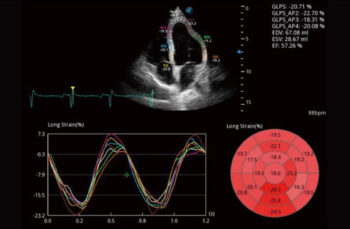

Миокардийн тоон шинжилгээ (MQA)

Миокардийн механикийн нарийн тоон хэмжилтийг MQA-ээр дамжуулан хийдэг бөгөөд энэ нь хананы хөдөлгөөнийг бодит цагийн мэдрэмжтэй хянахад үндэслэдэг. Энэ нь деформаци, деформаци, шилжилт хөдөлгөөн, хурд гэх мэт үнэлгээг өгдөг.